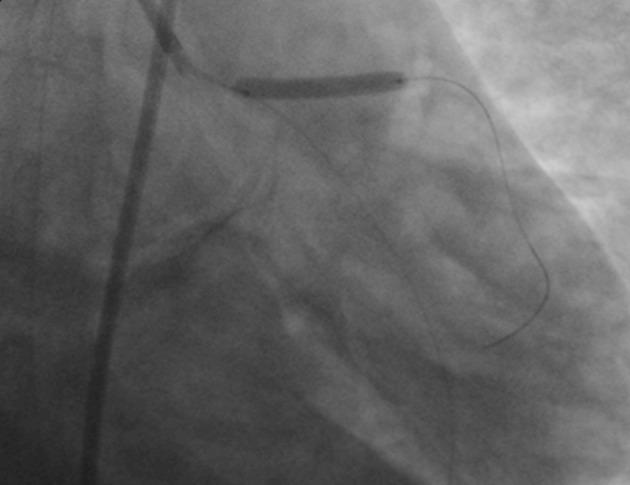

Myocardial Infarction in a Young Patient After Acute Exposure to Carbon Monoxide.

https://cdn.ncbi.nlm.nih.gov/pmc/blobs/49e6/5018305/aa923edcbe2c/aapm-06-03-33154-g001.jpg